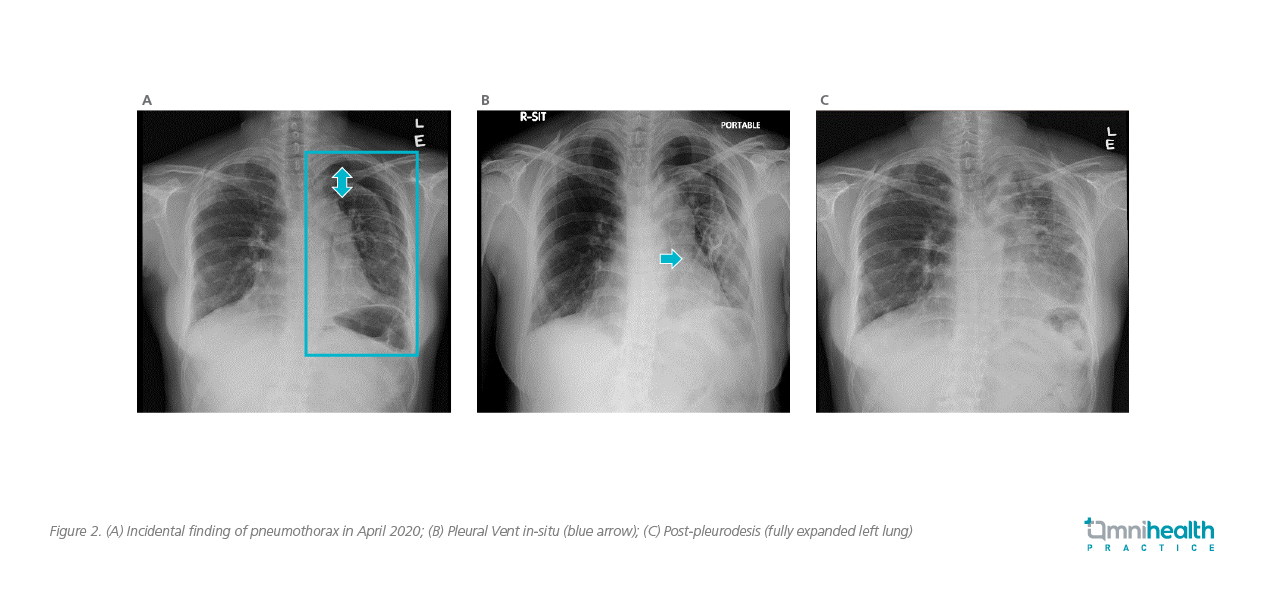

Dr. Lui shared a case to demonstrate the clinical effectiveness of ambulatory device in the management of selected patients with SP. A non-smoking female patient in her thirties had a past medical history of haematological malignancy and autologous stem cell transplant 10 years ago. She was diagnosed with pleuroparenchymal fibroelastosis 5 years after the transplant. In a follow-up visit, she was found to have a left sided apical pneumothorax (3cm from apex, figure 2A). Due to her underlying lung disease, a diagnosis of secondary SP was made. The patient did not experience any significant worsening in breathlessness and had a peripheral arterial oxygen saturation (SpO2) of 97% on room air. However, in view of her underlying chronic lung disease with fair lung function reserve, she was admitted to hospital for further monitoring.

Since the patient was minimally symptomatic, conservative management was adopted initially with supplementary oxygen. However, there was no radiological improvement after 3 days of conservative treatment. After thorough discussion, she was reluctant for placement of traditional larger-bore chest tubes. An 8-French Pleural Vent was then installed with a 5mm skin incision (figure 2B). She was kept in hospital for monitoring after the Pleural Vent was placed, which was connected intermittently to wall suction via the side port on the device. She was ambulatory in the ward with the Pleural Vent in-situ. The lung gradually re-expanded over the subsequent 5 days. Talc slurry pleurodesis was administered through the Pleural Vent upon full lung re-expansion, and the patient was discharged 12 days after installing the Pleural Vent (figure 2C).